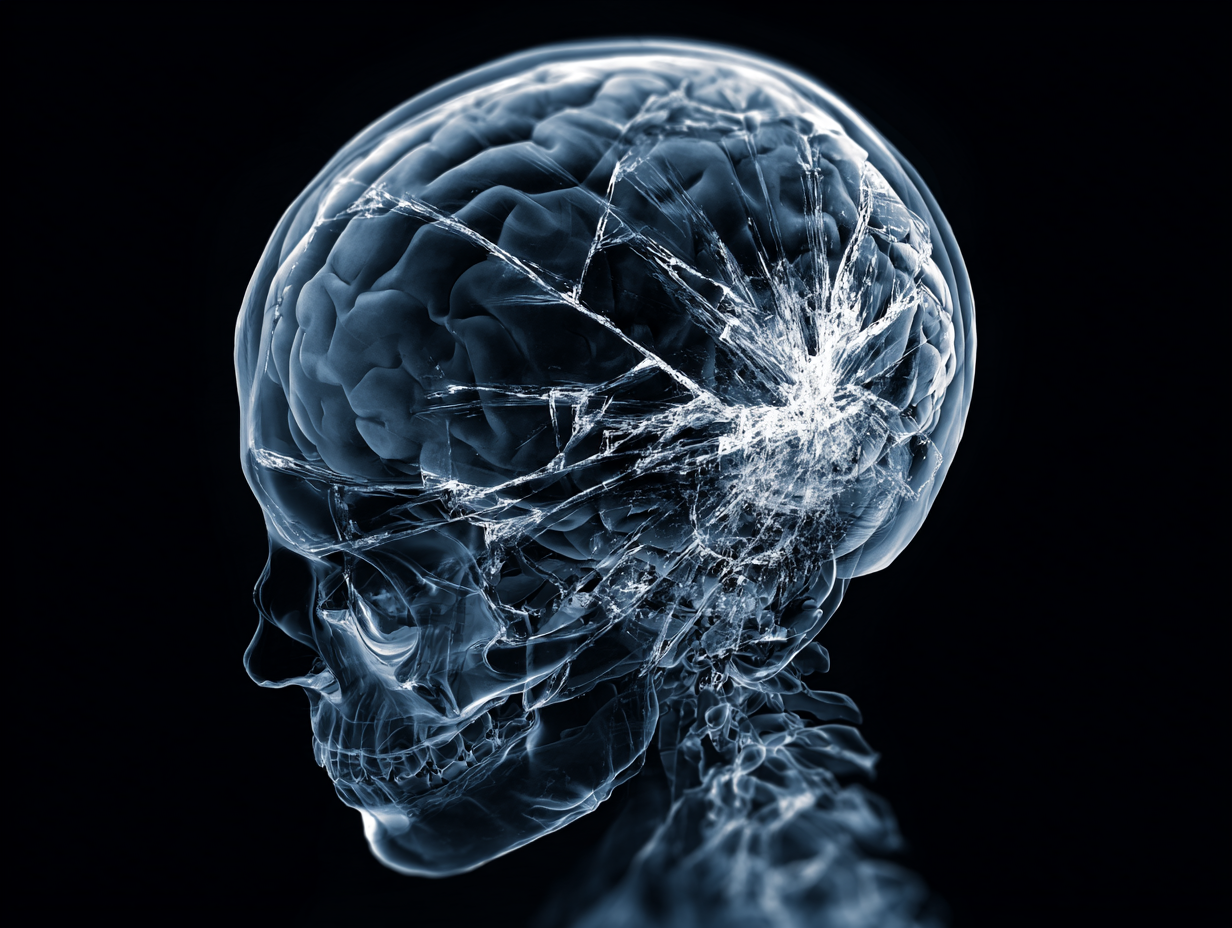

Forensic Neuropsychological Evaluations for Personal Injury (Including Traumatic Brain Injury)

Expert TBI Assessment: Specialized testing for concussion and brain injury.

Assess Injury Impact: Scientifically measure cognitive and emotional changes following TBI, concussion, stroke, or medical trauma.